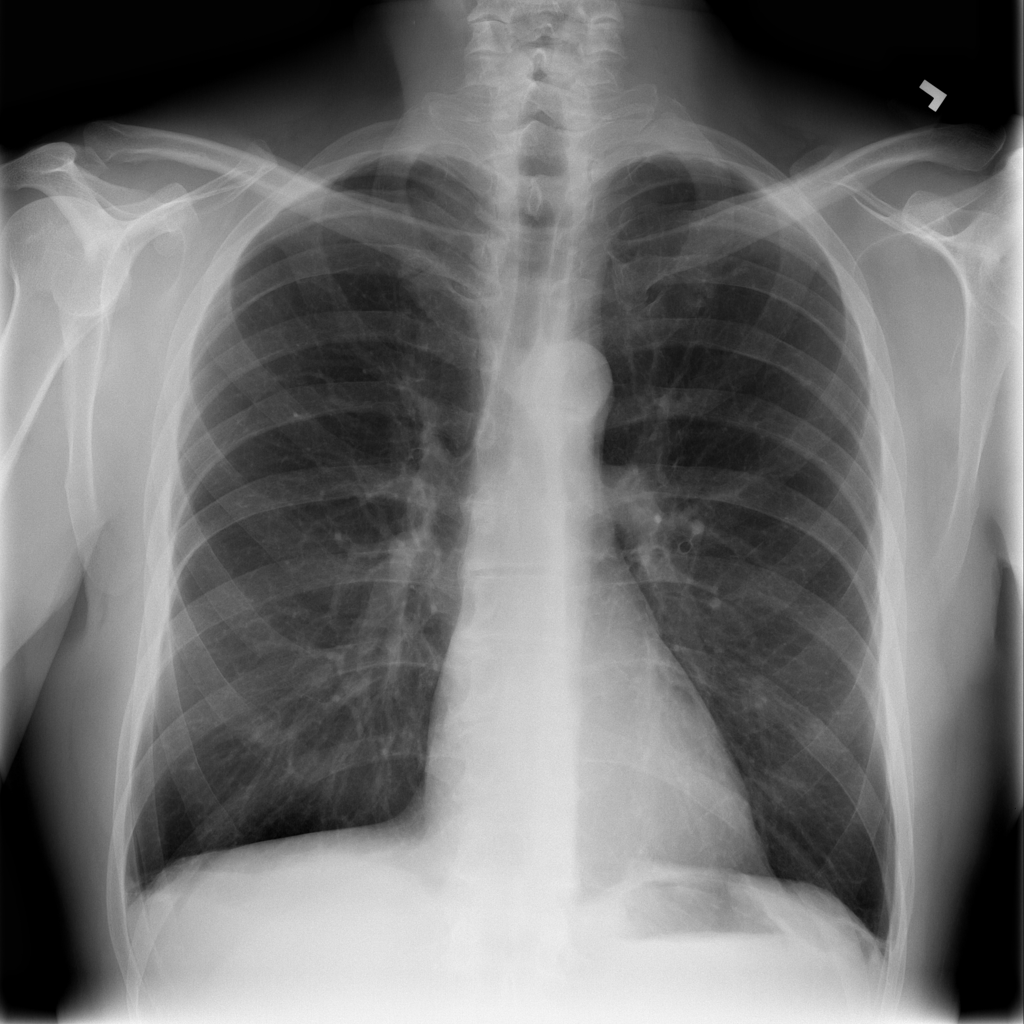

PAT-89B6 · IMG-004Emphysema

PAT-89B6 · IMG-004

PA